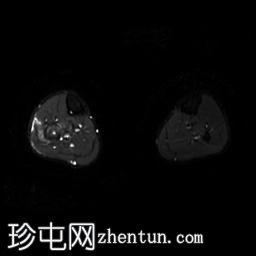

轴位

T1加权像